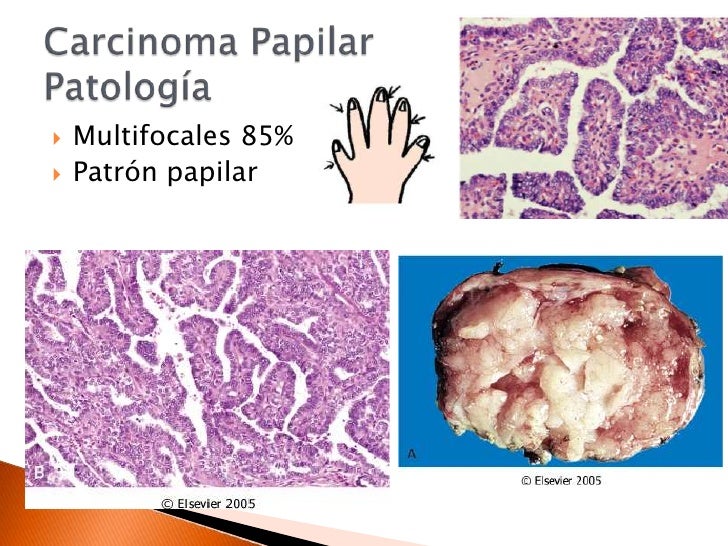

Carcinoma papilar de tiroides

V Congreso Virtual Hispanoamericano de Anatomía Patológica CARCINOMA